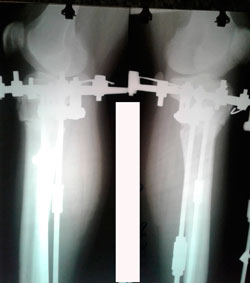

Дата операции - 16.03.2020

Дата снятия аппаратов - 30.06.2020

image-01-07-20-04-11-1.jpg

image-01-07-20-04-11.jpg